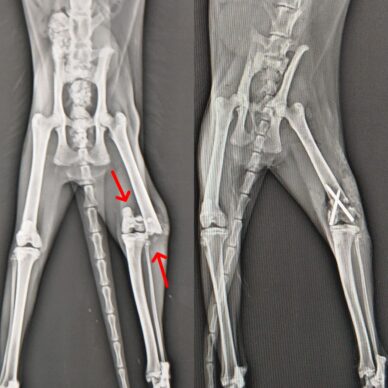

Ortopedi Cerrahi

Kedi ve köpeklerde ortopedi cerrahisinde başarı